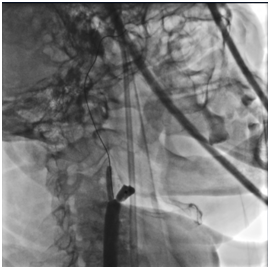

В область остаточного стеноза позиционирован и имплантирован самораскрывающийся каротидный стент с «закрытой ячейкой» d= 8-6 L=40 мм, с последующей постдилатацией стентированного сегмента баллонным катетером d=6 L=20 мм инфляцией 8 атм.

Выполнена аспирация 60 мл крови через систему церебральной протекции с получением атеросклеротического дебриса до получения «чистой» крови. Поочередно произведено снижение давления в дистальном и проксимальном баллонах системы, антеградный кровоток по правой ВСА восстановлен. Интракраниальные отделы хорошо кровоснабжаются из бассейна правой сонной артерии.

Общее время перекрытия правой ОСА составило 12 минут.